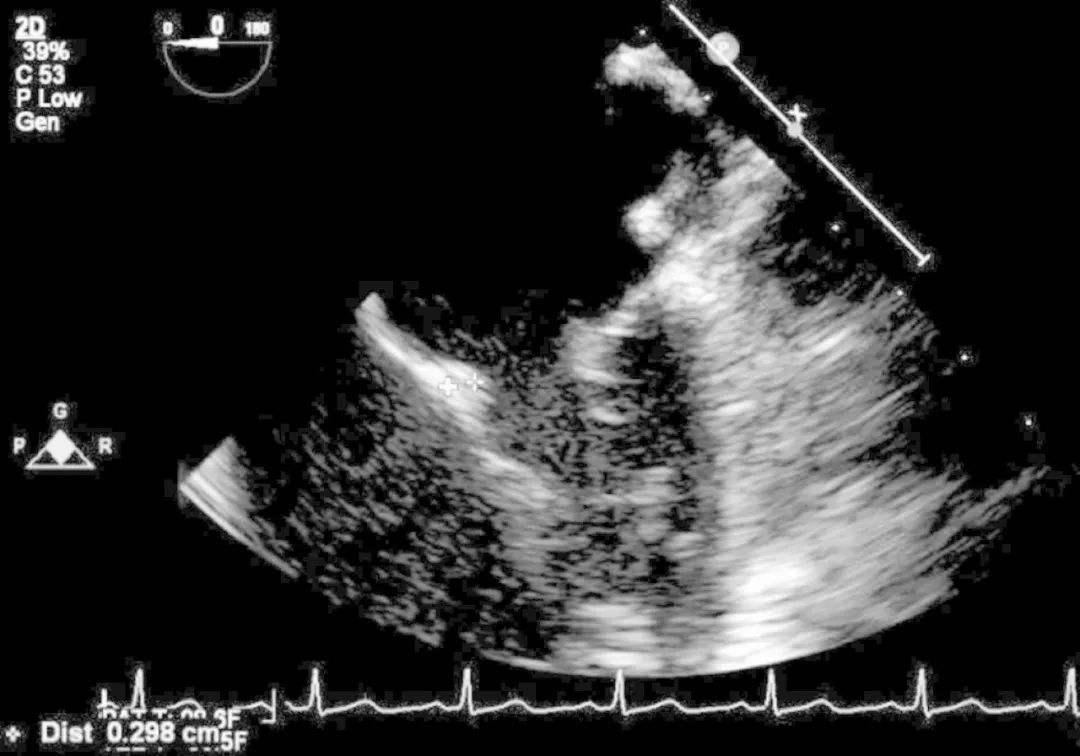

二尖瓣前叶有0.298cm的赘生物(图6),二尖瓣后叶有柄,二尖瓣反流严重。